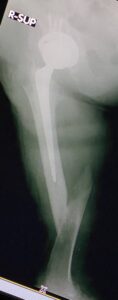

- Περιπροθετικό κάταγμα στην περιοχή στο πέρας του εμφυτεύματος ισχίου σε θήλυ ασθενή .

- Εσωτερική οστεοσύνθεση με πλάκα με αλληλοεπικάλυψη των εμφυτευμάτων για να μην υπάρχουν υψηλές συγκεντρώσεις φορτίων (stress risers)

- H οστεοσύνθεση σε οστεοπορωτικoύς ασθενείς αρχίζει από το γόνατο με σωστή εφαρμογή του εμφυτεύματος και φθάνει μέχρι το ισχίο για να μην υπάρχουν stress risers.

Tα περιπροθετικά κατάγματα σε ηλικιωμένους πρέπει στην οστεοσύνθεση να περιλαμβάνουν ολόκληρο το μήκος του οστού, με αρκετή ελαστικότητα, προάγοντας έτσι την πώρωση και διατηρώντας ταυτόχρονα την σταθερότητα του συστήματος.